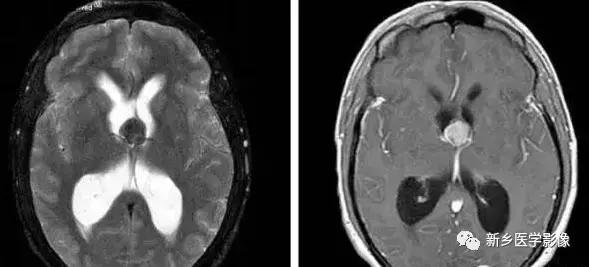

5.脑室周围白质软化症

主要与缺血缺氧及感染有关.常见于早产儿.是造成早产儿脑瘫的主要原因。由于脑室周围白质的血供分别来自脑室区和远脑室区的终动脉。未成熟儿终动脉深穿支的侧支循环尚未建立,而胚胎晚期脑室周围白质对缺血缺氧敏感。所以,脑室周围自质软化症多见于早产儿。由于病灶常为双侧性,故双侧侧脑室多同时扩大。脑白质内软化灶在CT扫描时表现为白质内斑片状低密度灶.MR T1加权图呈低信号,T2加权图呈高信号。

由于侧脑室周围有软化萎缩,故扩大的侧脑室外缘常不规则,不光整,这种不规则、不光整是本病引起脑室扩大的特征,另外,本病均表现有脑白质量减少及脑白质内斑片状软化病灶,脑白质减少严重时表现为部分区域白质消失,脑皮层与脑室侧缘接近甚至相连。CT表现为斑片状低密度灶。MR T1WI上呈低信号,T2WI呈高信号。